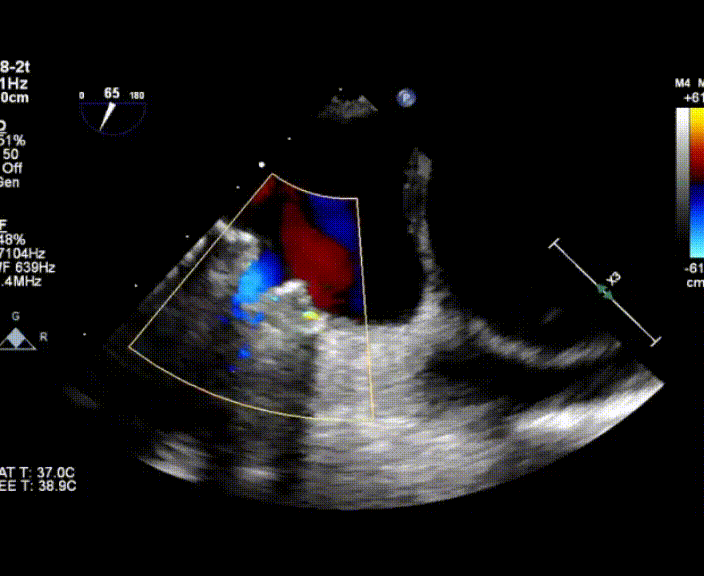

超聲心動(dòng)圖提示:右心增大,右室肥厚,左室測(cè)值偏小,房間隔中份探及修補(bǔ)術(shù)后回聲,房水平未見(jiàn)殘余分流,三尖瓣重度反流,重度肺動(dòng)脈高壓,中度肺動(dòng)脈瓣反流,左室收縮功能測(cè)值正常,右室收縮功能減低 。

術(shù)中首先在局麻下穿刺股動(dòng)脈、股靜脈,完成心導(dǎo)管檢查評(píng)估后轉(zhuǎn)為全麻,在食道超聲引導(dǎo)下穿刺房間隔,穿刺成功后將加硬導(dǎo)絲送入左上肺靜脈建立軌道,根據(jù)患者病情行球囊預(yù)擴(kuò)張后植入6mm孔徑房間隔造孔支架,經(jīng)透視及食道超聲評(píng)估支架左右盤(pán)展開(kāi)良好,夾持于房間隔兩側(cè),固定穩(wěn)定、位置良好,食道彩超顯示房水平右向左為主分流,分流孔直徑符合預(yù)期大小,心導(dǎo)管檢查評(píng)估達(dá)到預(yù)期效果,釋放造孔支架。術(shù)后12h患者下床活動(dòng),恢復(fù)順利,擬于近日完善術(shù)后評(píng)估后出院。